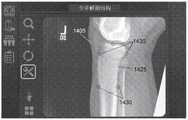

图13A-13B示出了根据实施例的相对于至少一个2D图像缩放和重新定向3D骨模型的过程。13A-13B illustrate a process for scaling and reorienting a 3D bone model relative to at least one 2D image, according to an embodiment.

图14示出了根据实施例的修改3D骨模型的轮廓的过程。14 illustrates a process of modifying the contour of a 3D bone model, according to an embodiment.